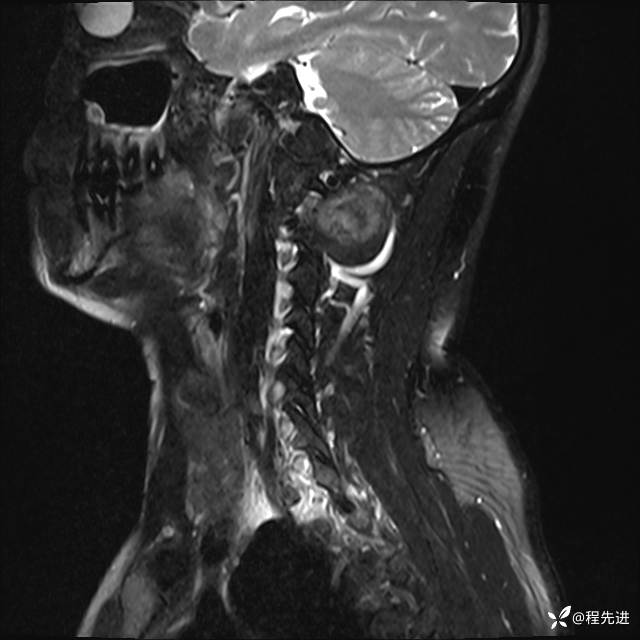

MRI平扫+增强:

T2: